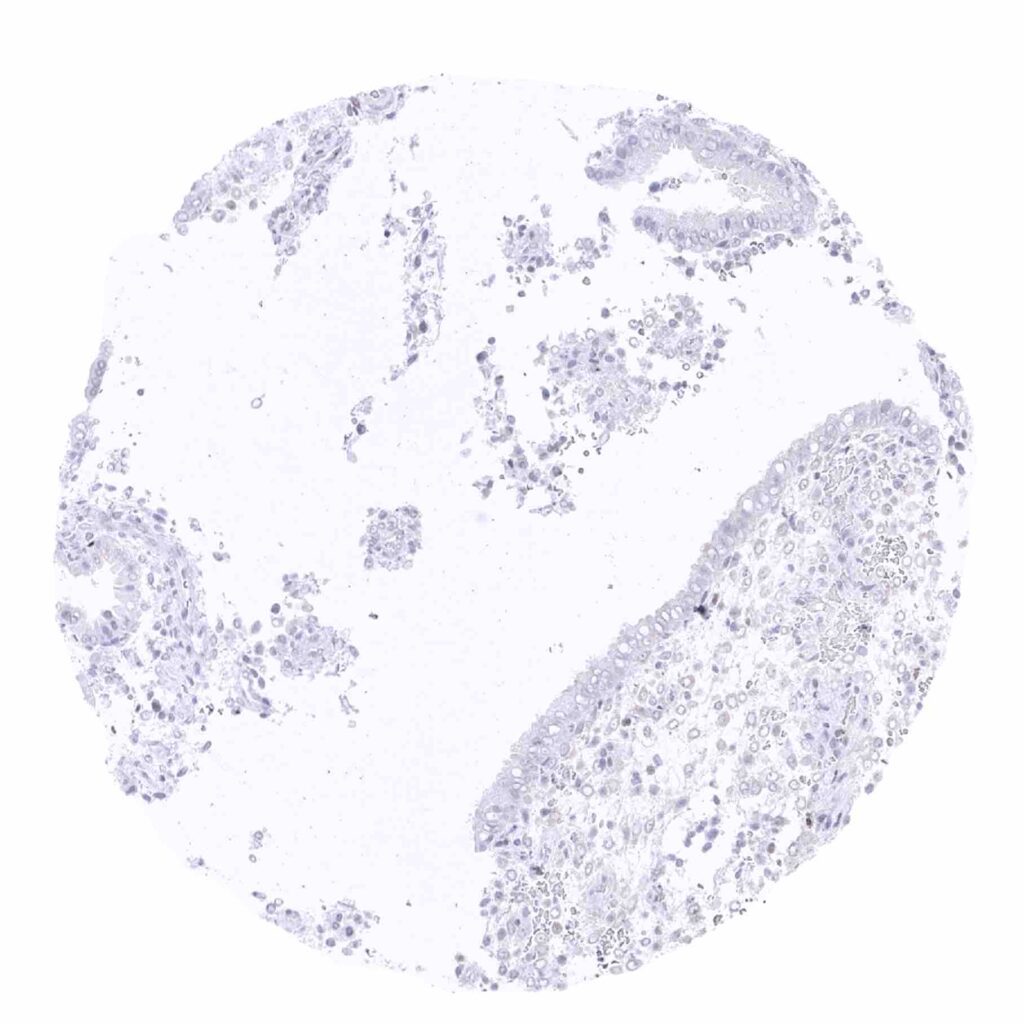

Lymph node – Weak to moderateTFE3 staining of a seizable subset of sinusoidal cells (macrophages_)